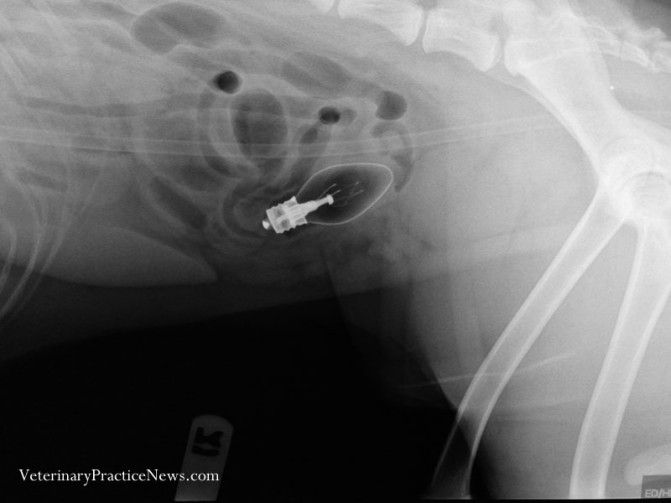

Az anyuka nem értette, hová tűnnek a gyerek játék kacsái

Egy darabig csak vette az újabb és újabb kacsákat, amíg egy nap a saját szemével nem látta, ahogy a család kutyája elfogyasztja a legújabb darabot. Azonnal indultak az állatorvoshoz, aki egy komoly, ötdarabos kacsagyűjtemény mellett egy játék traktortól és egy azonosítatlan játék alkatrésztől is megszabadította a falánk jószágot.